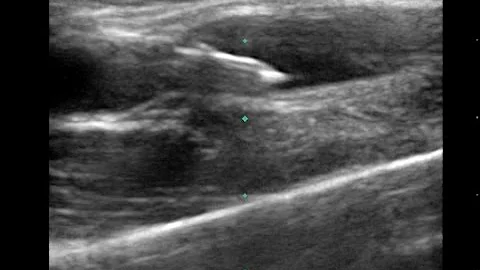

Pocus Guided Vascular Access Fundamentals: In-plane, Long Axis

This brief video details techniques for obtaining vascular access with POCUS guidance using an out-of-plane technique, targeting ...